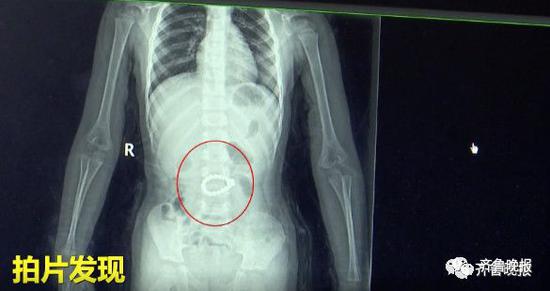

3岁男童肚子疼打针都无效 医生拍片发现异物(图

拍片一看右上腹有一个手镯样异物...